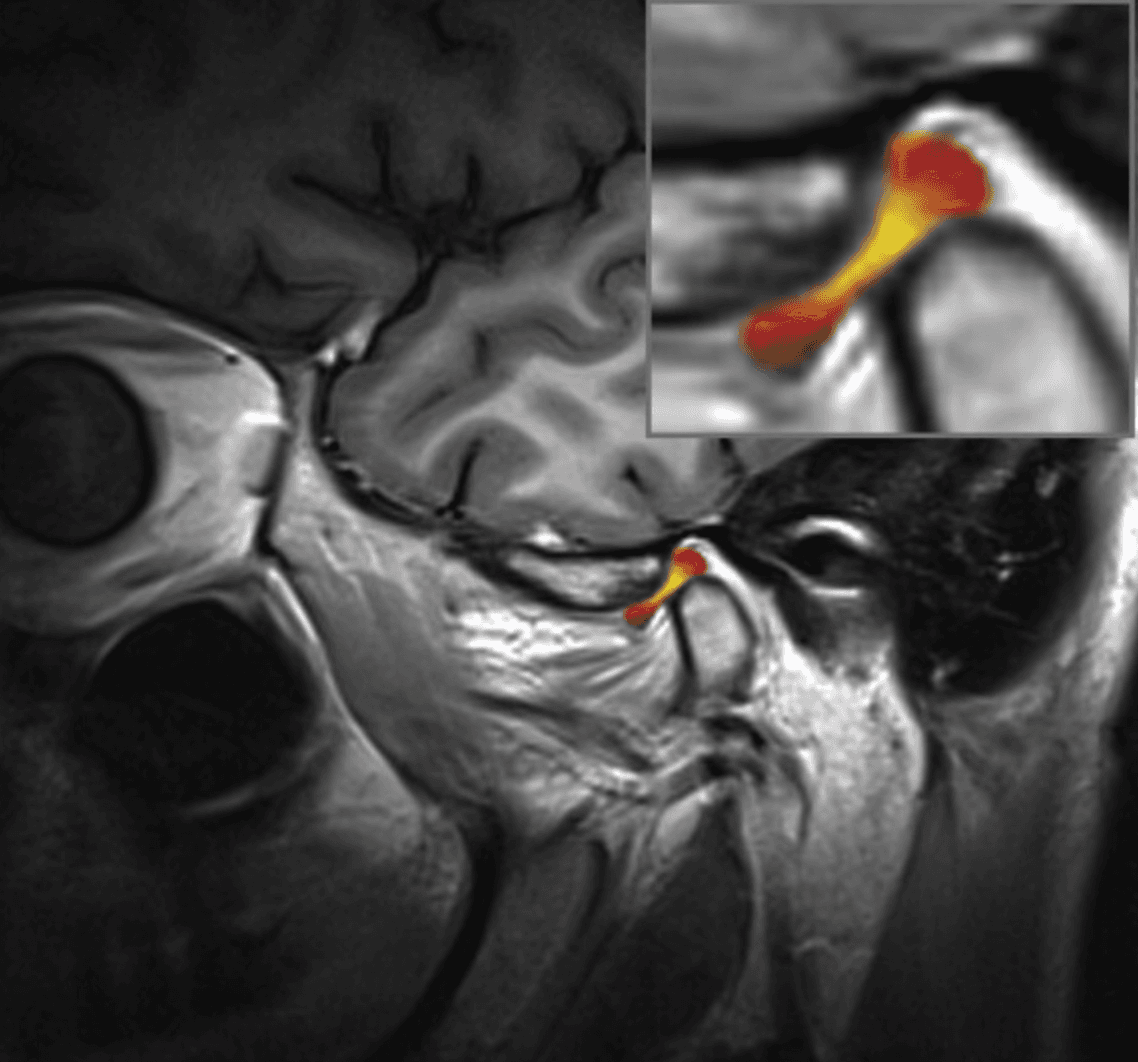

Le chirurgien maxillo-facial joue un rôle important dans le traitement des désordres temporo-mandibulaires (DTM), qui sont des affections affectant les articulations temporo-mandibulaires et les muscles qui contrôlent le mouvement de la mâchoire. Cela peut se manifester par différents symptômes allant de douleurs orofaciales, une interférence ou une limitation dans l’ouverture, un blocage en position fermée ou ouverte ou encore des cliques et craquements articulaires. Le chirurgien maxillo-facial est formé pour évaluer et diagnostiquer les DTM, en utilisant des techniques d'examen clinique, d'imagerie médicale (comme la radiographie, l'IRM ou la tomodensitométrie) et parfois des tests spécialisés pour évaluer la fonction de l'articulation temporo-mandibulaire.

Certains DTM par contre nécessiteront une approche chirurgicale en raison de leur nature ou de l’impact significatif qu’ils ont sur la fonction. En règle générale, le chirurgien tend à choisir l’approche minimalement invasive qui est la plus appropriée dans les circonstances. Cela peut impliquer une simple infiltration articulaire, une chirurgie sous caméra (arthroscopie; approche qui permet d’avoir accès et manipuler le contenu articulaire sans avoir à ouvrir) ou dans certains cas une chirurgie ouverte (arthrotomie). Les Drs Poirier et Badri détiennent notamment des expertises dans ces champs de pratiques de par leur expérience et leur surspécialisation.